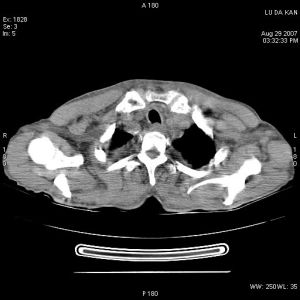

可發現肺部原發病灶、縱隔增寬或肺門淋巴結增大。胸部CT或MRI檢查

有助於明確上腔靜脈阻塞的原因。其他